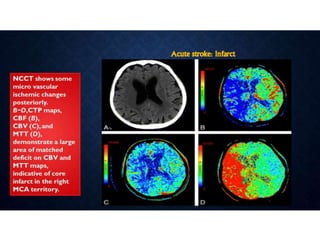

ACUTE STROKE IMAGINGPROTOCOL • When acute stroke patients present within 6 hours of the onset of symptoms - un-enhanced CT or with conventional/MR imaging. • Hemorrhage at unenhanced CT or >1/3 MCA territory - not treated with thrombolytic drugs. • Ischemia of < 1/3 MCA territory, those who present <3 hours after the onset of acute stroke - intravenous thrombolytic drugs • 3–6 hours after the onset of symptoms - CT angiography and CT perfusion imaging to assess the intracranial and neck vessels and detect any penumbra. • Intraarterial therapy is usually considered for patients in whom a penumbra is seen. • Patients in whom no penumbra is seen are not usually treated with thrombolytic drugs

CTP IN STROKE •• Stroke is a leading cause of mortality and morbidity in the developed world. • • The goals of an imaging evaluation are • I. to establish a diagnosis as early as possible • II. to obtain accurate information about the intracranial vasculature • III. to identify critically ischemic or irreversibly infarcted tissue (“core”) and to identify severely ischemic but potentially salvageable tissue (“penumbra”). • This information can guide triage and management in acute stroke.